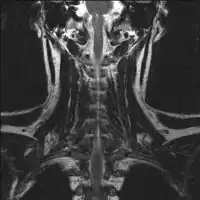

Solitary plasmacytoma in the long bone of the upper arm

Skeletal surveys are used to ensure there are no other primary tumors within the axial skeleton. MRI can be used to assess tumor status and may be advantageous in detecting primary tumors that are not detected by plain film radiography. PET-CT may also be beneficial in detecting extramedullary tumours in individuals diagnosed with SPB. CT imaging may be better than plain film radiography for assessing bone damage.[6][7]